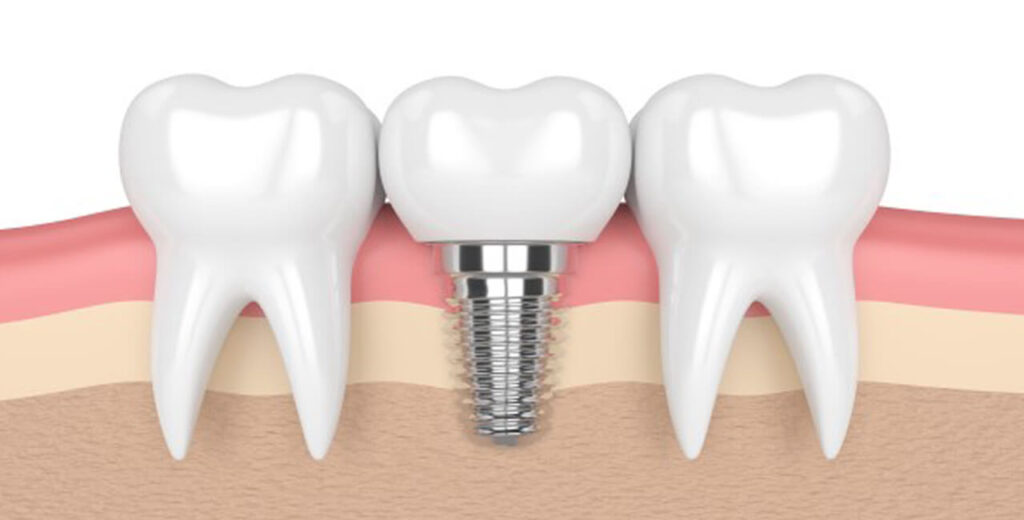

Overview of Implantology

We are a professional and affordable dental practice in Hyderabad offering an extensive range of dental services at the Hospital, including cosmetic, orthodontic, periodontic, endodontic, implant and cosmetic teeth whitening treatments, other specialist dental services.